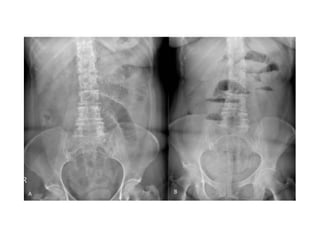

• La triada clásica de

obstrucción en el examen

radiológico es:

o Asas de intestino delgado dilatadas

(mayores a 3 cm)

o Niveles hidroaéreos

o Ausencia de aire distal

Signo del “grano de café”

Hallazgo clásico y diagnóstico del vólvulo sigmoideo en una radiografía simple de abdomen